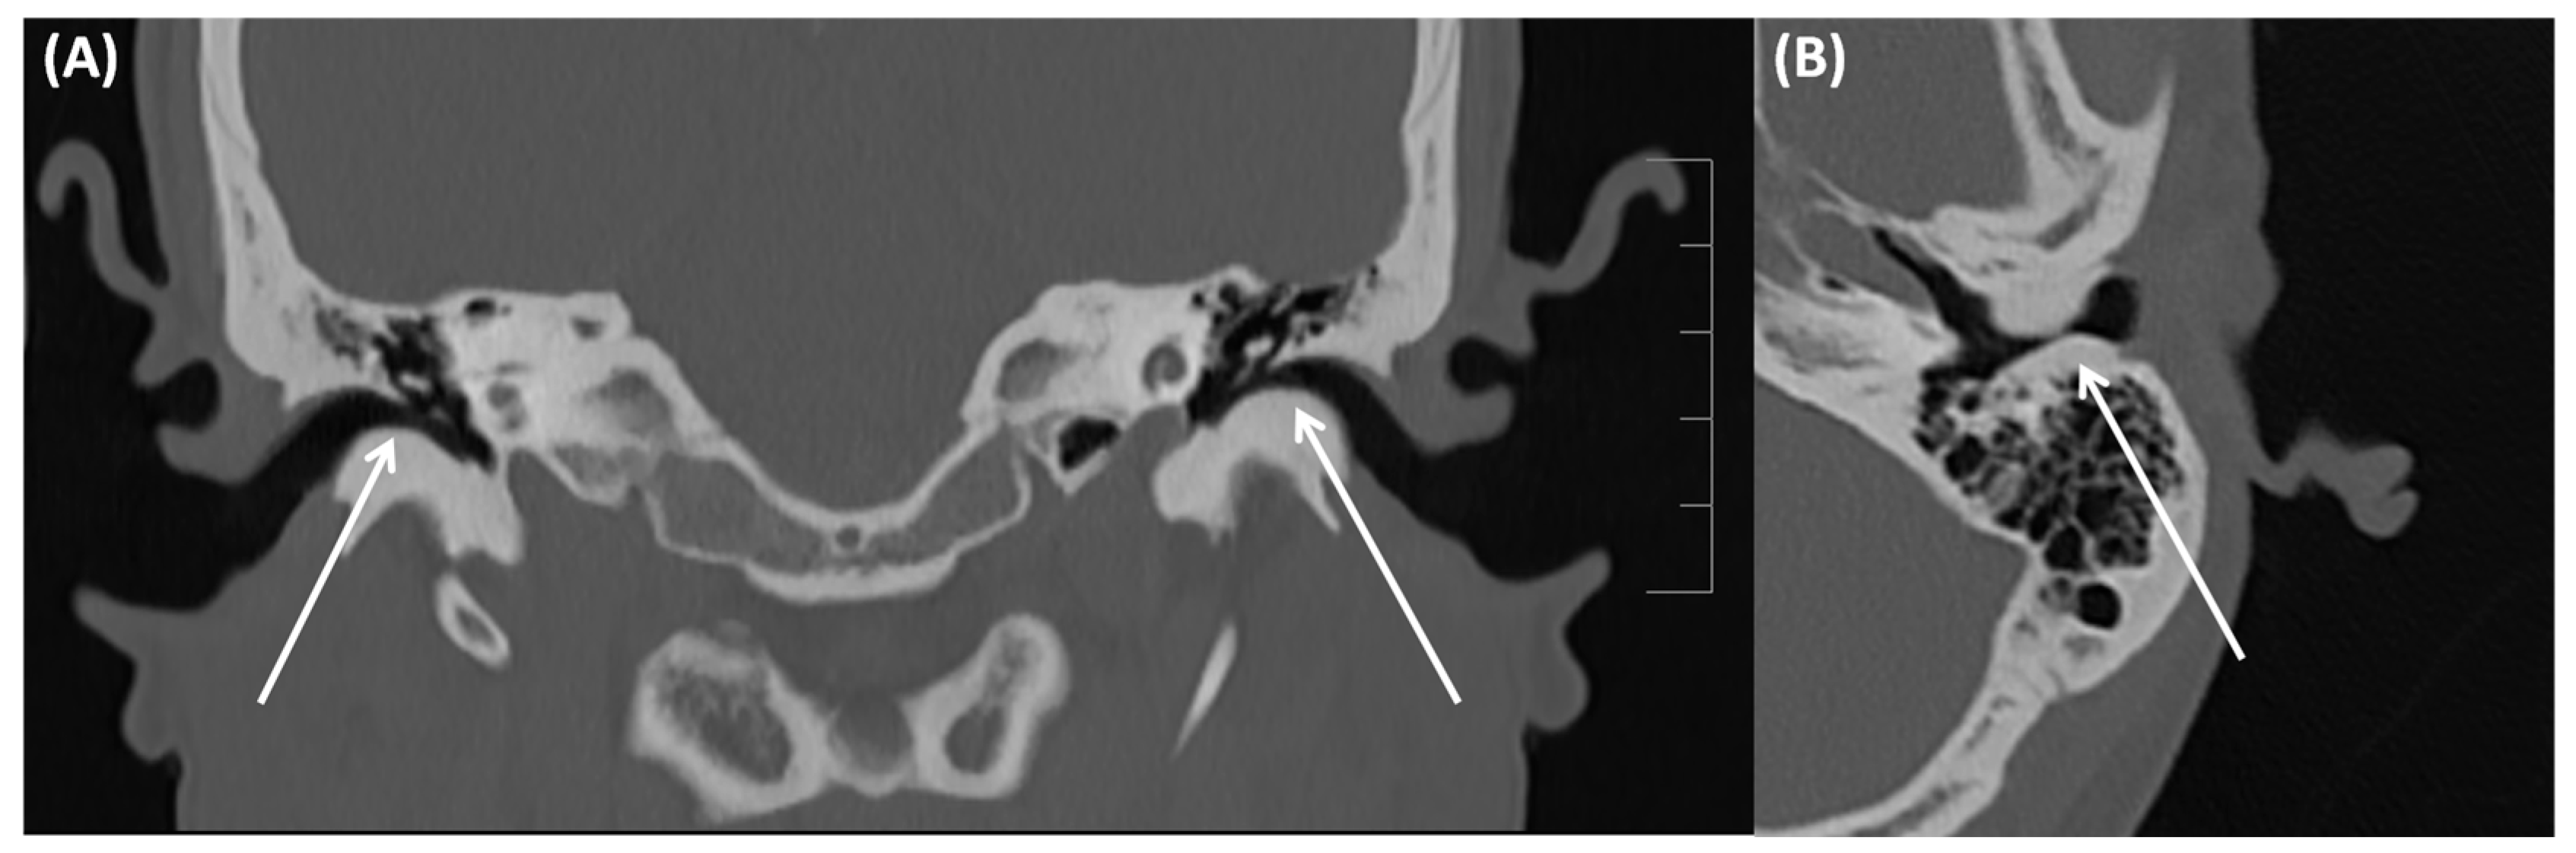

3.1.3. Auditory Canal Exostosis